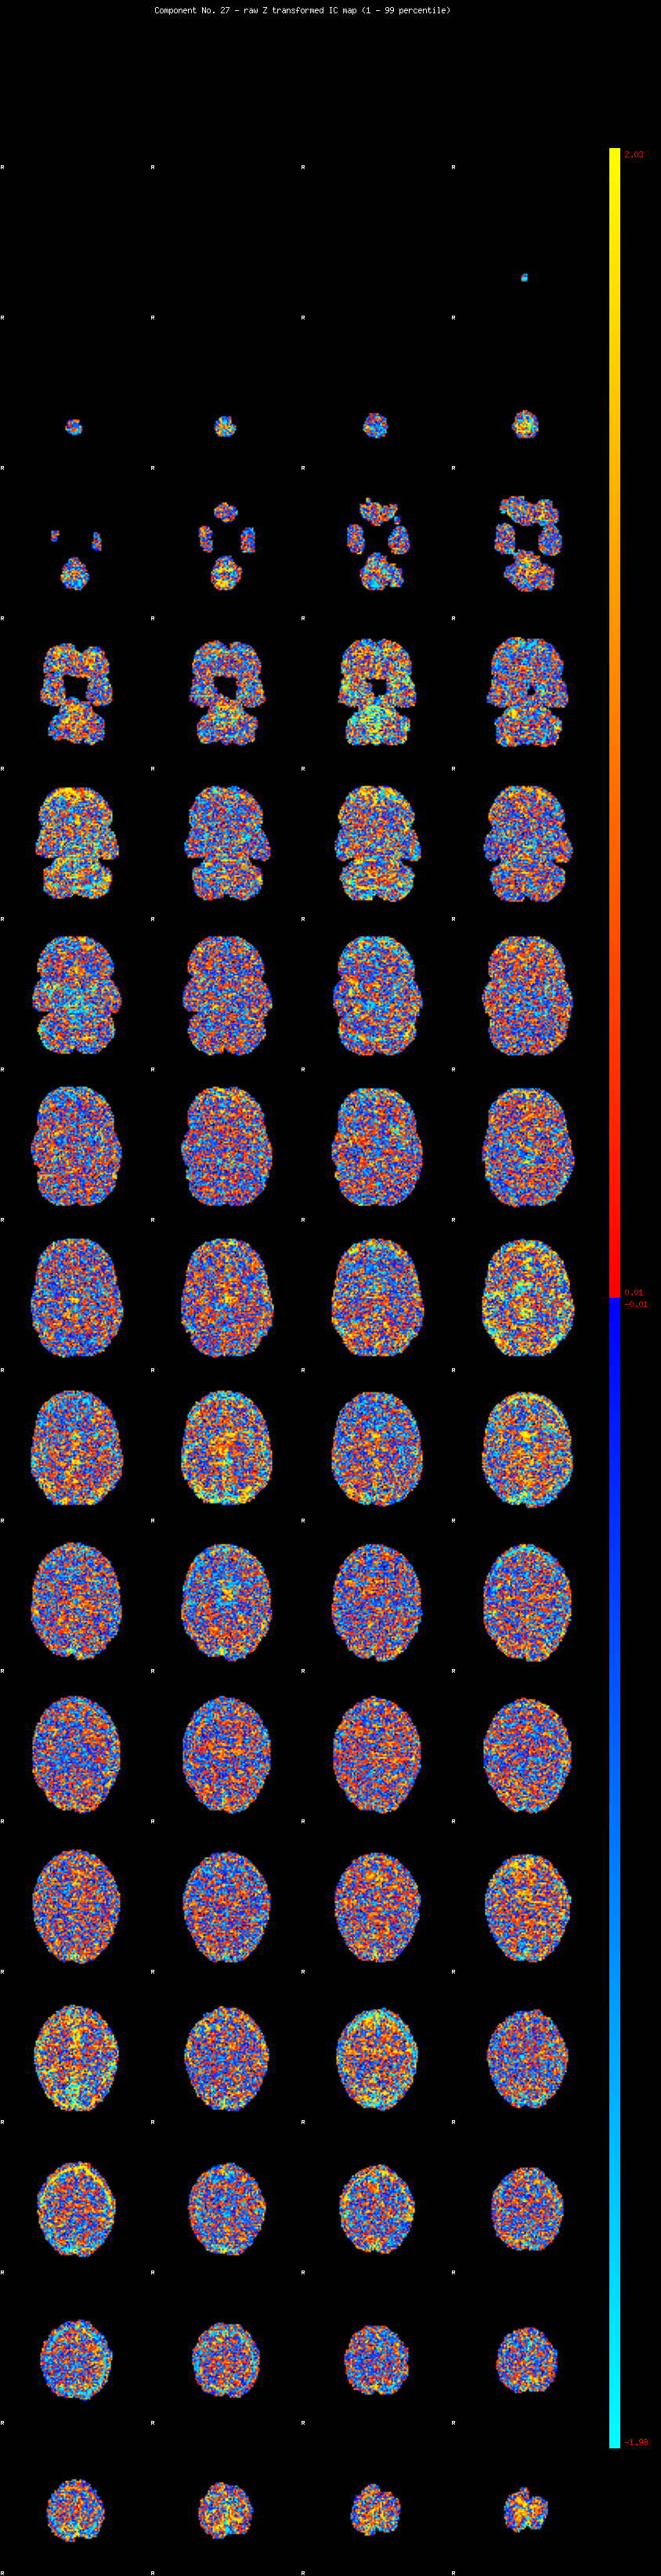

IC_27 Mixture Model fit

Means : 0.000000 2.426278 -2.287118

Vars : 1.000000 1.816460 1.411063

Prop. : 0.926806 0.038188 0.035006